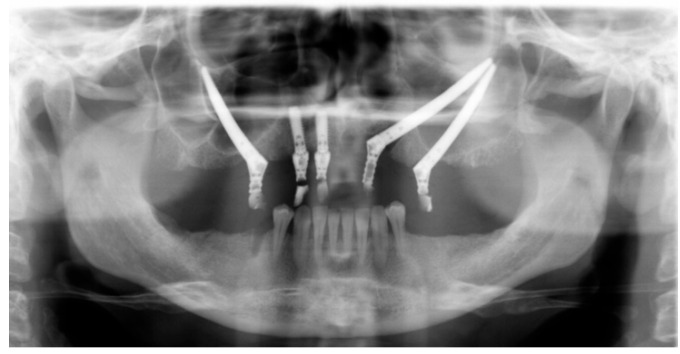

Methods: The 55-year-old patient was treated with placement of 3 ZIs, two on the left side. Left periorbital swelling with pain appeared 10 days after surgery with progressive worsening of symptoms. After antibiotic treatment, she developed a left cutaneous fistula with purulent discharge. CT showed two ZIs on the left side with the apical portions in close contact with a 1 cm-wide portion of resorbed zygomatic external cortex and a layer of granulation tissue.

Results: Due to the limited amount of bone involved by the fixation tip, the left ZIs were removed and the skin fistula repaired. The patient healed without complications but required prosthesis replacement.